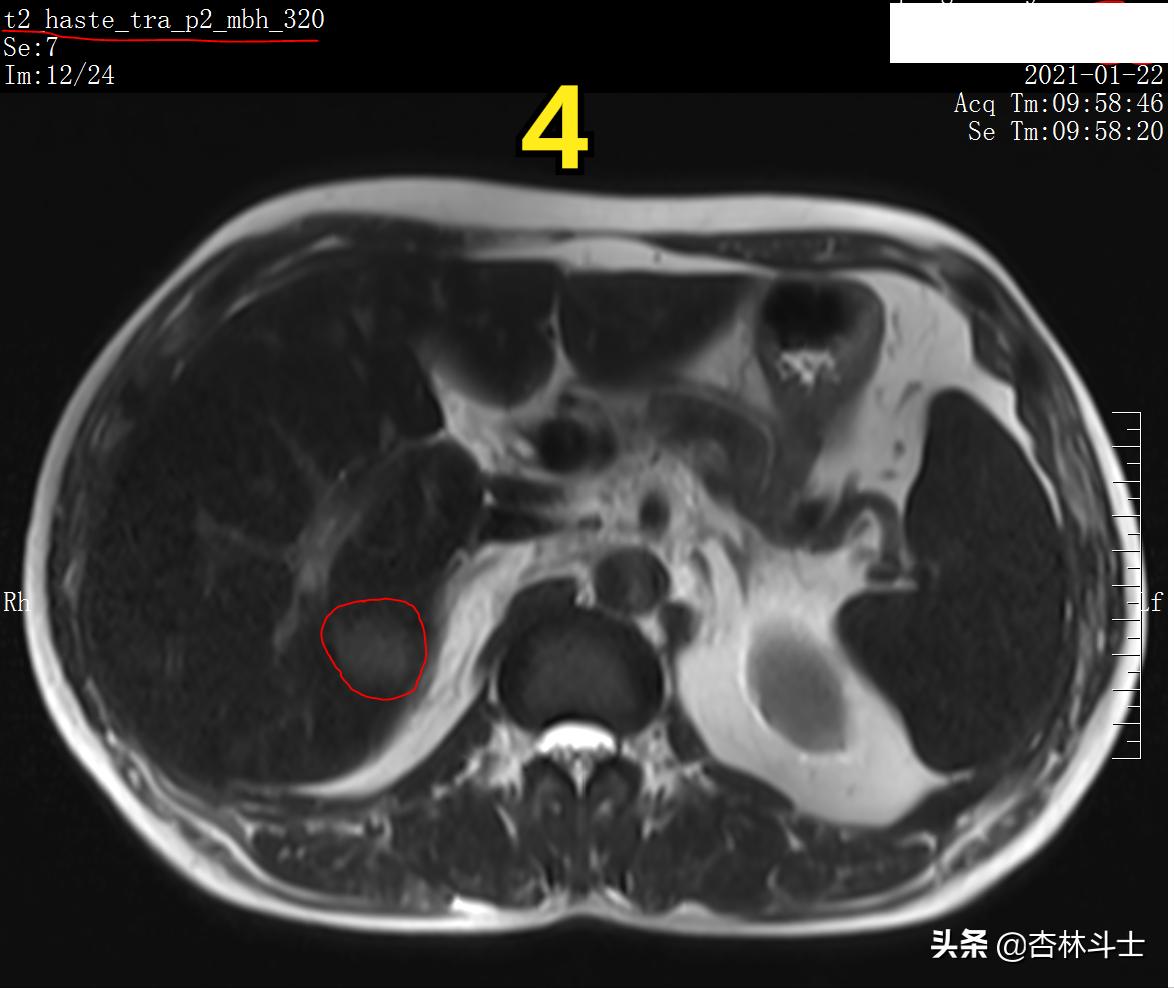

图4 T2加权像

图4 T2加权像 病灶呈稍高信号影,余肝实质内未见明显肝硬化再生结节,从磁共振图像上分析患者肝硬化程度不重。